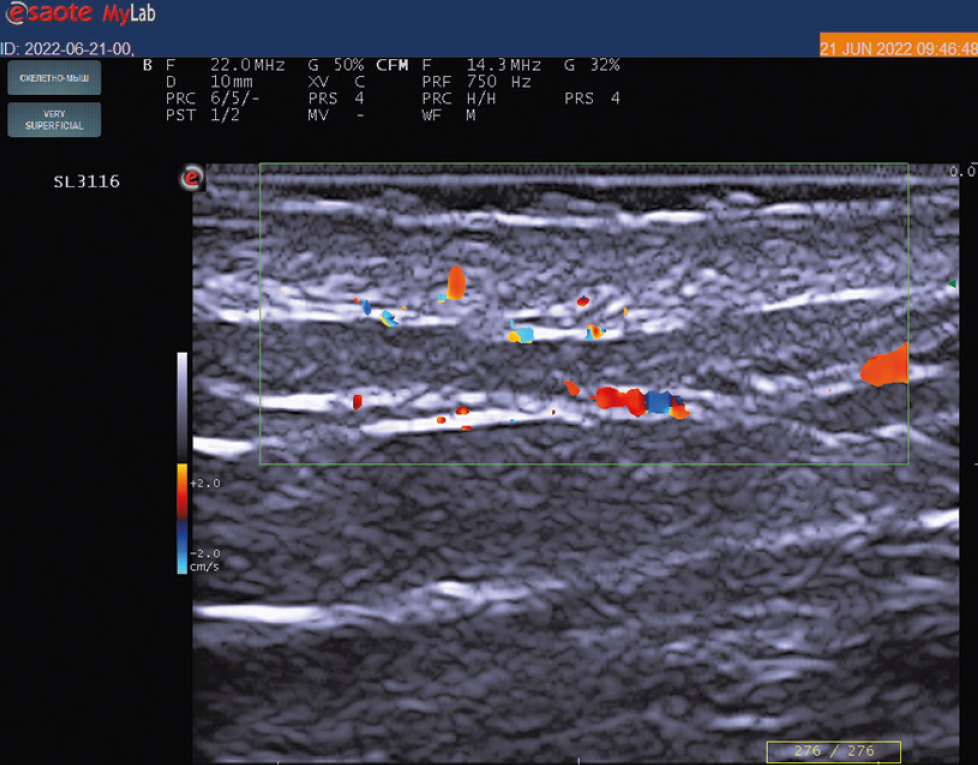

При оценке первичного энергетического допплерографического ультразвукового исследования кожи в области псориатических бляшек отмечены признаки повышения кровотока в сосочковом и сетчатом слоях кожи в виде множественных изолированных и сливных допплеровских сигналов по сравнению с отсутствием подобных сигналов в неповреждённой коже (рис. 2, 3). У большинства обследованных (47; 57,3%) наблюдались признаки II (умеренной) степени повышения кровотока, у 23 (28%) ― I (минимальной) степени, у 12 (14,6%) ― III (выраженной) степени. Среднее значение шкалы градации степени повышения допплеровского энергетического кровотока у пациентов при первичном исследовании составило 1,87.

Рис. 2. Ультрасонография с применением датчика 22 МГц (частота допплера 14,3 МГц, частота повторения импульсов 750 КГц): крупные допплеровские сигналы сливного характера в дерме в области псориатической бляшки, соответствующие II степени повышения кровотока.

Fig. 2. Ultrasonography using a 22 MHz transducer (doppler frequency 14.3 MHz, pulse repetition rate 750 KGz of signals): Large doppler signals of confluent character in the dermis in area of psoriatic plaque, corresponding to the II degree of increased blood flow.